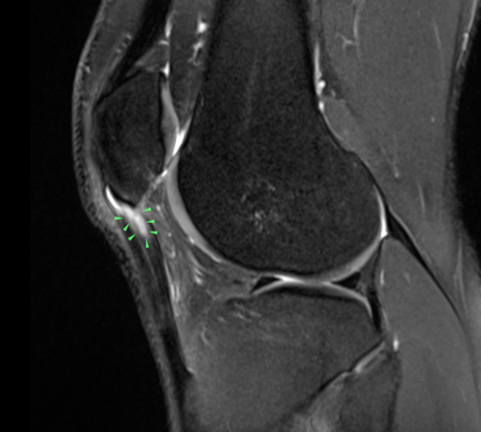

- MRI & Ultrasound Scanning may be required for further detail